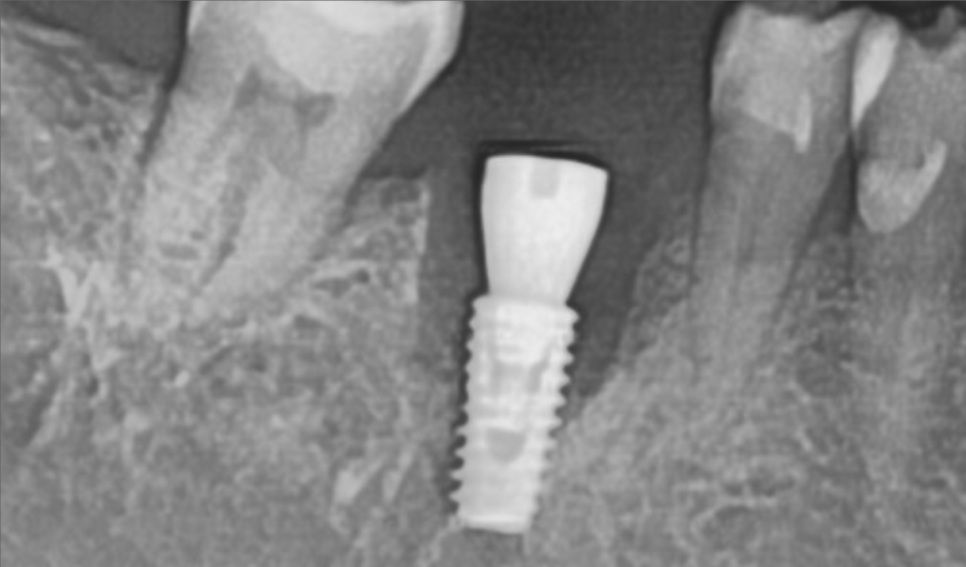

2달이 지났습니다. 임플란트가 잘 붙은것을 확인하고

임플란트 상부 보철물 제작을 진행합니다.

반대편에 고름주머니 잡힌 치아도 발치 즉시 식립으로 수술을 원하셔서

당일 수술 진행해 드렸습니다.

(이랫던 치아가... 30분이 지나면..)

요렇게 바뀝니다.

CT상으로 봐도 잘 들어갔군요.

주변부 뼈의 양도 골질도 매우 괜찮습니다.